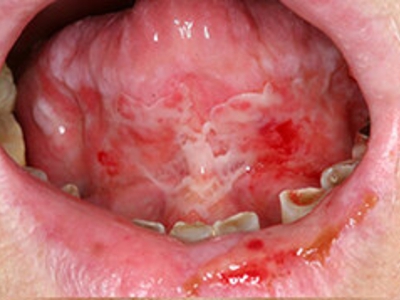

副肿瘤性天疱疮是一种罕见的累及皮肤黏膜的自身免疫大疱性疾病,常伴发肿瘤。肿瘤多为淋巴增生性肿瘤,可累及多个内脏器官,其特征性临床表现为疼痛的口腔黏膜炎和多形性皮疹,患者常因口腔黏膜糜烂疼痛首次就诊,本病好发于中青年,但亦可见于学龄前儿童及老年人,无明显性别差异。

1、黏膜皮肤损害:副肿瘤性天疱疮常以口腔黏膜炎为首发症状,表现为广泛、难治性的溃疡、水疱、糜烂等,患者口唇分泌物增加、疼痛,拒食,常见口唇糜烂、渗血、血痂等;病变部位除口腔黏膜外,亦可累及眼结膜、咽喉部、呼吸道、肛周生殖器等部位。少数患者以皮疹为首发症状,皮损呈多形性,常泛发于头颈部、前胸后背和肢体近端。皮损随病情加重及缓解动态变化,同一人可见不同类型皮损。掌趾部常可见脱屑、红斑、水疱、溃烂及指甲损害、甲沟炎、甲脱落、甲周红肿等。